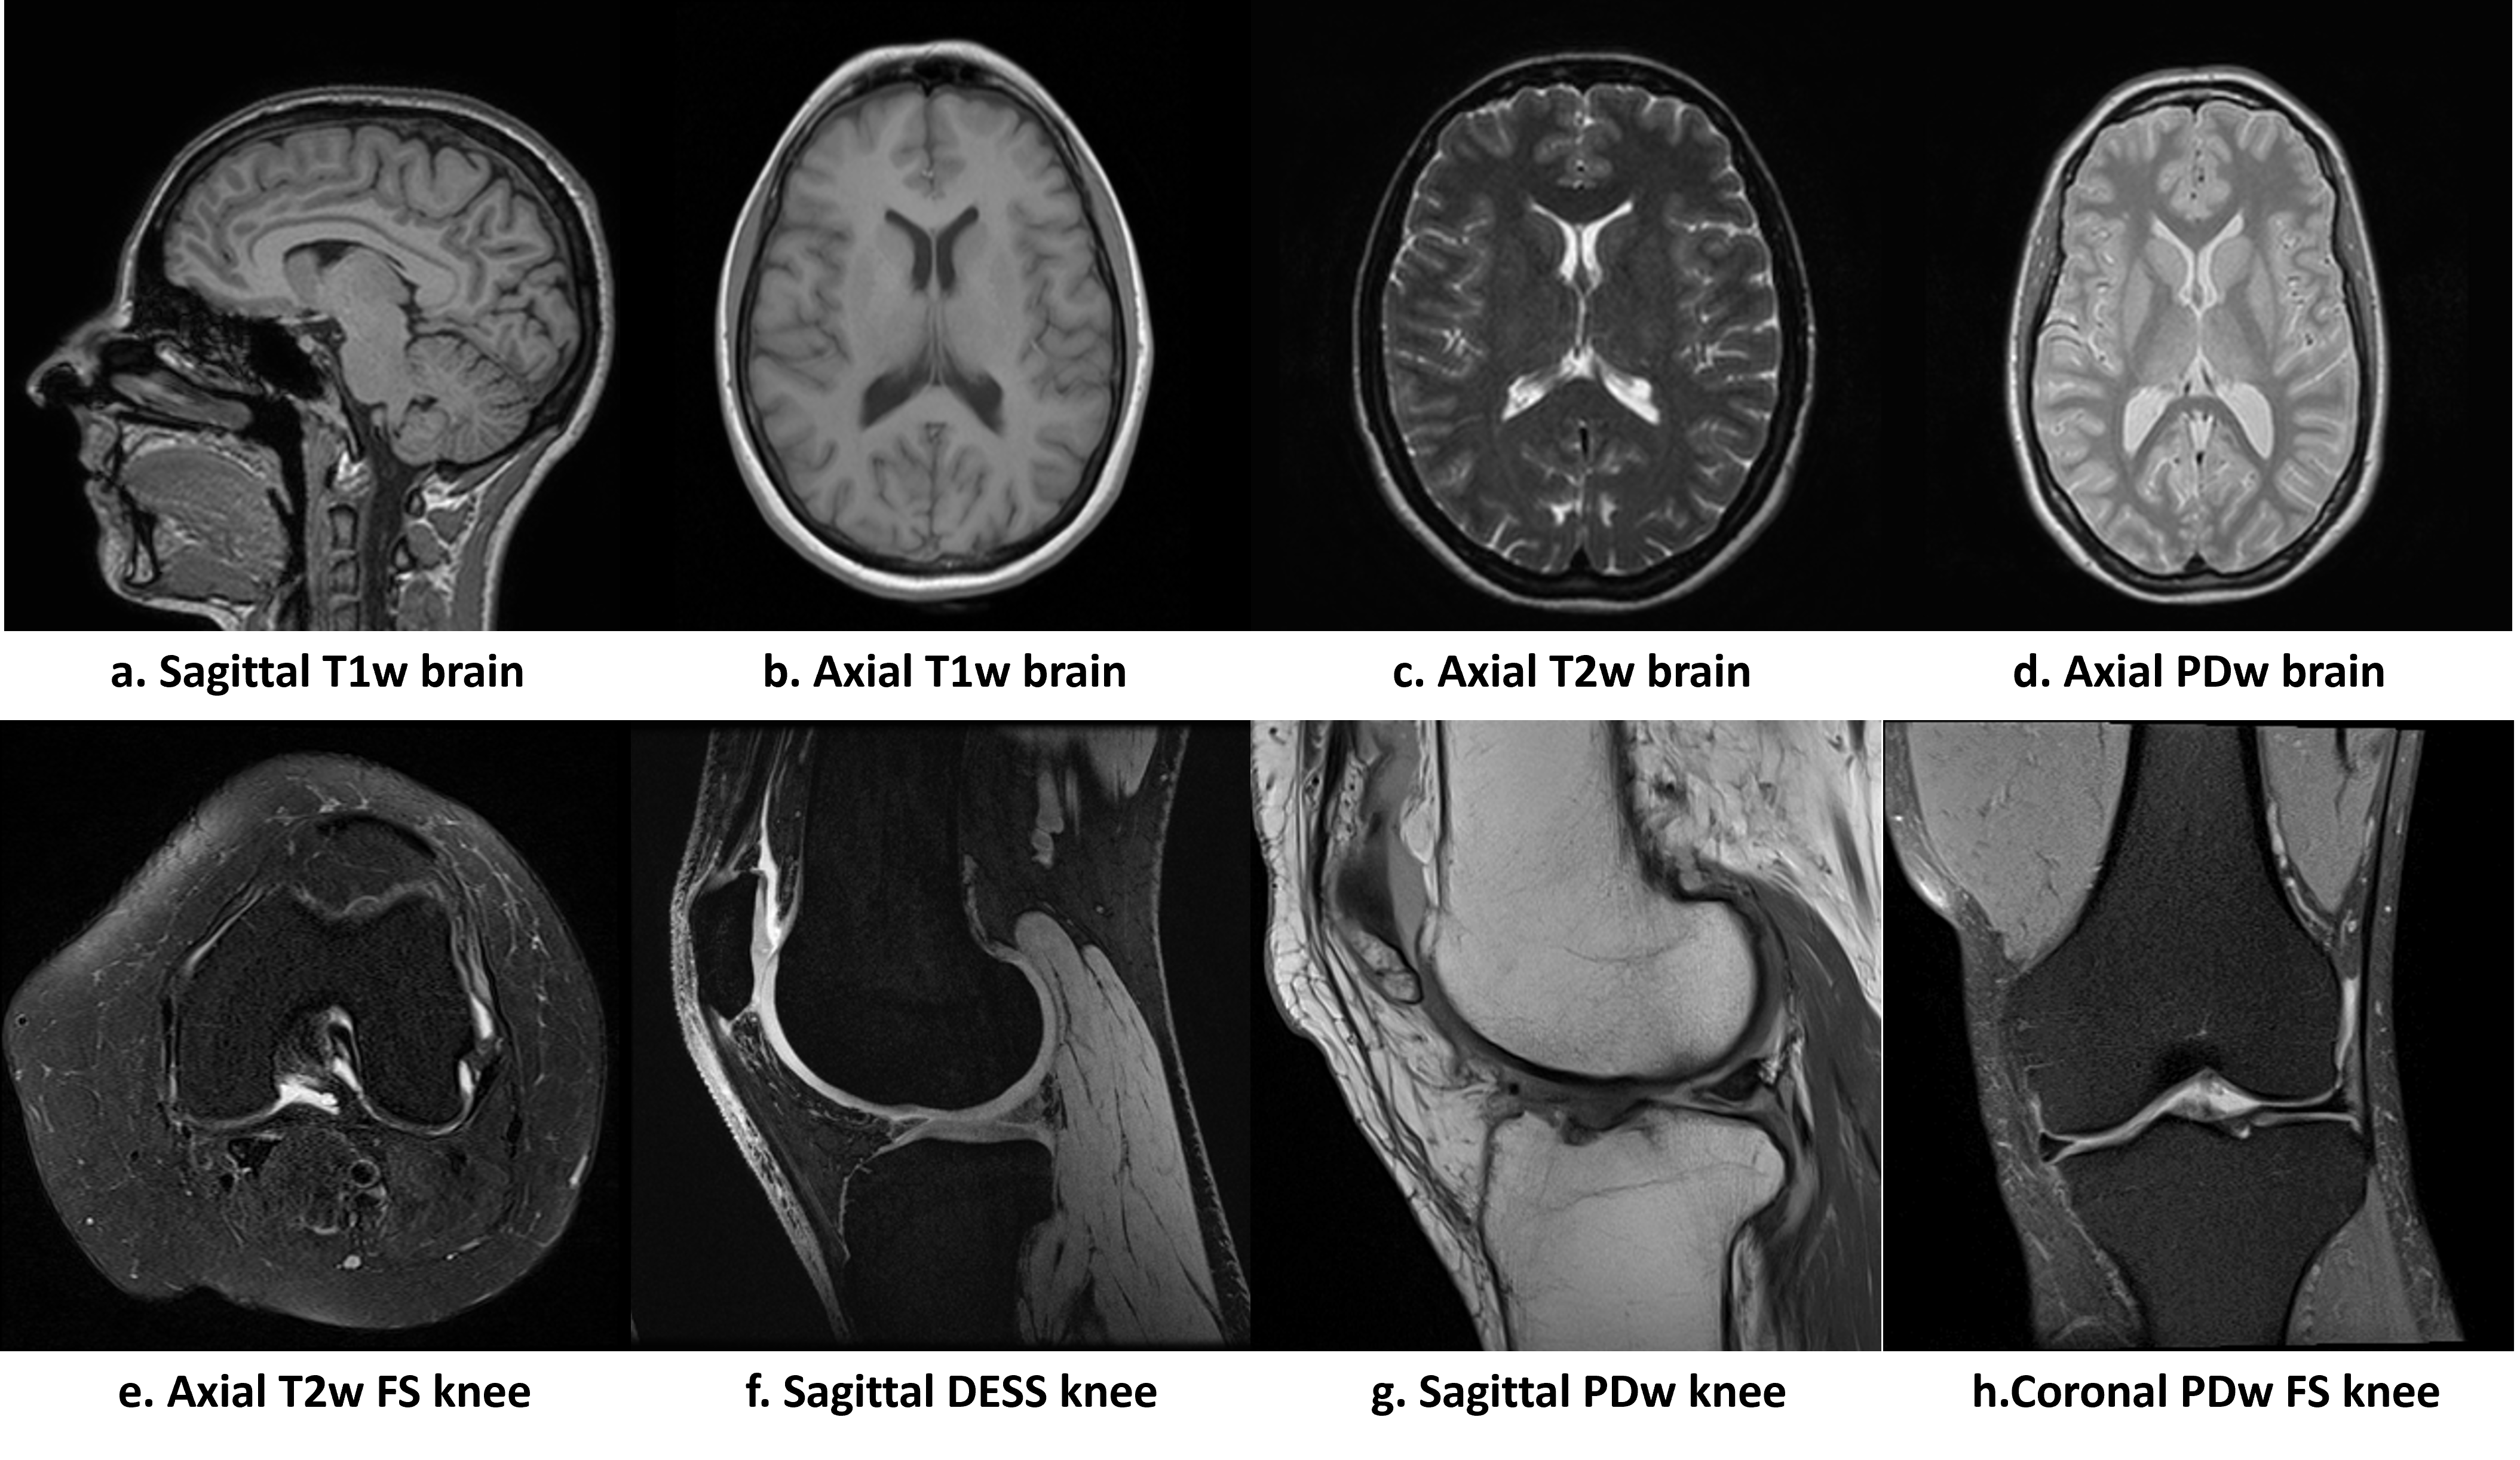

Refer to caption

Figure 1: MR images of various views, anatomies and acquisition protocols acquired on different machines. a and d are from IXI database; b, c, e, g and h are from fastMRI database [15, 28]; and f is from SKM-TEA database [3].

MR images present various appearances based on different acquisition protocols, imaging views, scanning parameters, manufacturers, etc. Fig. 1 shows examples of MR images with diverse appearances. When comparing b,c and d, we can observe that for axial brain images, varying acquisition protocols results in differences in brightness, contrast and saturation. This image style variations with acquisition protocols can also be observed by comparing f and g. In addition, due to the hardware differences, images acquired on different machines with divergent scanning parameters present variant noise levels and resolutions. The same subject with different views also shows dissimilar structures. All these differences during acquisitions result in different image styles, which can affect the performance of undersampled reconstruction algorithms [8, 17, 25, 31].